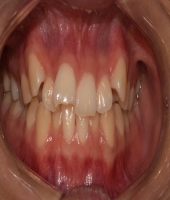

| ● 진료과목 : [심미보철] 돌출치아의 치료

| ● 내용 : 사고로 인한 돌출치아의 치료 |